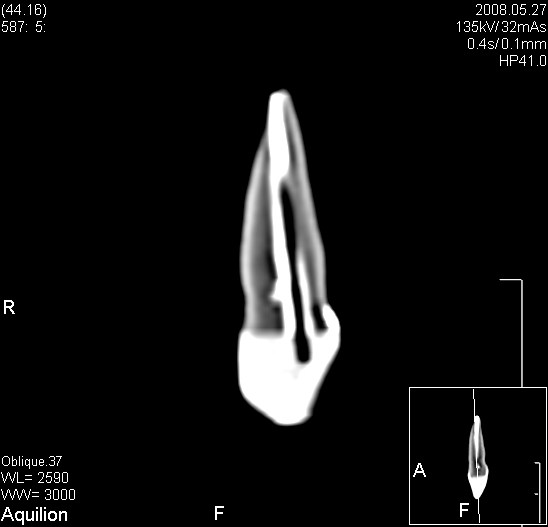

W naszej galerii pojawił się nowy, bardzo ciekawy przykład obliczeń wytrzymałościowych. To co ciekawe to fakt, że badaniom poddano ludzki ząb. Dokładniej zaś poddano badaniu wpływ różnych technologi i materiałów odbudowy uszkodzonego zęba na występujące w nim naprężenia. Praca jest ciekawa nie tylko na ze względu na swoją skalę ale i dla takich powodów jak doświadczalne potwierdzenie wyników symulacji numerycznych. Zaś dla pasjonatów fotografii cyfrowej ciekawostką z pewnością będzie informacja o zastosowaniu do tworzenia modelu geometrii i wewnętrznej budowy zęba zdjęć tomograficznych.